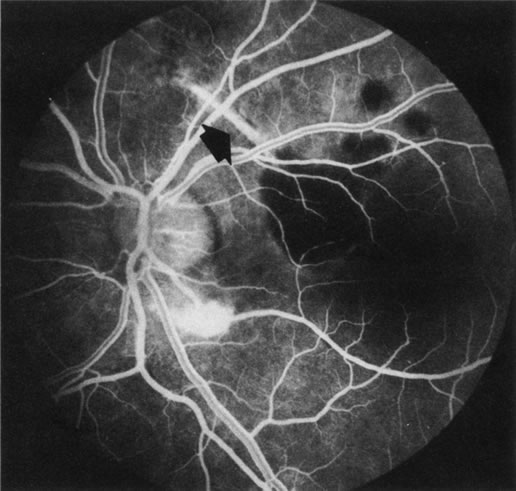

FA is also useful in characterizing two other subgroups of CNV: retinal angiomatous proliferation (RAP)8–16 and polypoidal choroidal vasculopathy (PCV).17–50 RAP begins in the deep retinal complex, forming intraretinal neovascularization (IRN), which may subsequently progress to extend beneath the neurosensory retina, forming subretinal neovascularization (SRN), and a vascularized PED.8 In the later phases of the process there may be a retinal-choroidal anastomosis (RCA). Clinical features of RAP include intraretinal hemorrhages, cystoid macular edema, and associated vascularized PED. FA is useful in revealing the presence of the angiomatous intraretinal vascular complex and the extension of the associated PED (Figs. 12 and 13). However, other diagnostic techniques such as indocyanine green (ICG) angiography, and optical coherence tomography (OCT) may be able to better demonstrate the presence of the RAP lesion.

Fig. 12. A. Clinical photograph of a retinal angiomatous proliferation (RAP) lesion (arrow). Note the intraretinal angiomatous proliferation, a feeding retinal arteriole, and a draining retinal venule, as well as the presence of intraretinal hemorrhages. B–C. Fluorescein angiography reveals late leakage from the RAP lesion.